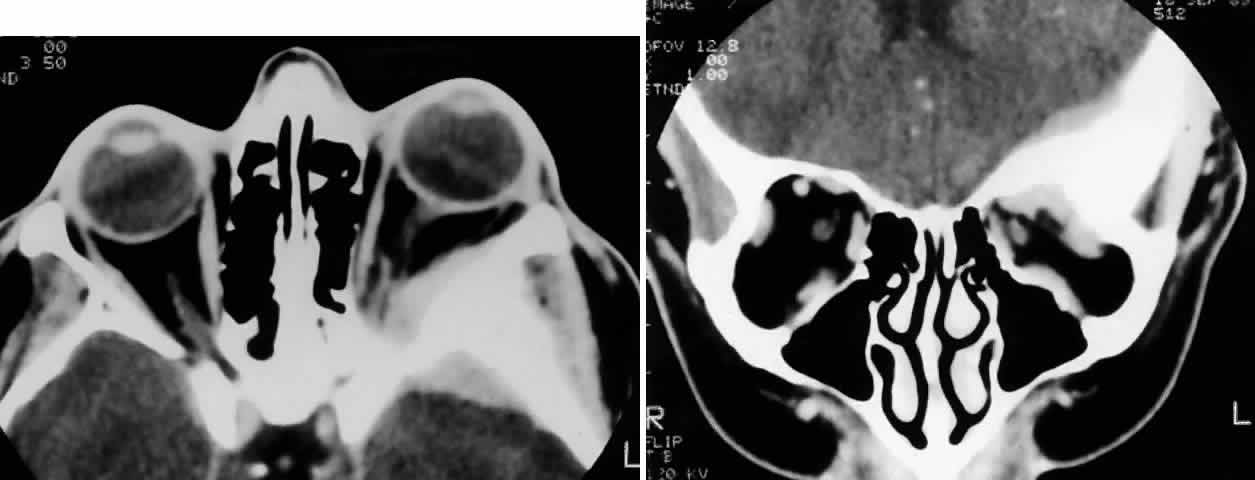

Fig. 4. A 36-year-old white woman presented with a 3-month history of progressive left proptosis associated with a retrobulbar pressure sensation. On external examination, she had bossing of the temporalis fossa and a proptosis of 9 mm axially, with a slight downward displacement of the globe. Ocular ductions were full, and there was no evidence of optic nerve compromise. CT scan on axial (A) and coronal (B) views confirmed a hyperostosing sphenoid wing meningioma with soft tissue components in the posterolateral orbit and anterior middle cranial fossa. During the next 20 months, her proptosis progressed to 11 mm, accompanied by increasing headaches and ocular pain, ocular restriction, and blurred vision in abduction. She underwent tumor resection with a combined frontotemporal orbitozygomatic approach, and she remains without evidence of recurrence 5 years after surgery. Visual function was preserved, and proptosis decreased to 2 mm.

Fig. 5. A 48-year-old Chinese woman had undergone previous frontotemporal craniotomy and partial excision of a left sphenoid wing meningioma. She presented 6 years later with progressive proptosis, visual loss, and numbness of the left cheek and upper teeth that developed during the preceding 2 years. On external examination, she had fullness of the temporalis fossa, an axial proptosis of 11 mm, and downward displacement of the left globe 2 mm (A). Ocular ductions were moderately restricted in all fields of gaze. She had no light perception, marked optic disc pallor, and an optociliary shunt vessel. CT scan revealed an extensive regrowth of meningioma involving the sphenoid wing, with soft tissue components in the temporalis and middle cranial fossae, parasellar region, and orbit, shown here on axial view (B). The lesion also involved the cavernous sinus and pterygopalatine fossa. She underwent a combined resection via the frontotemporal orbitozygomatic approach, followed by radiotherapy (50 Gy in 25 fractions over 5 weeks) for residual components in the cavernous and sphenoid sinuses. Two years after surgery, she remains comfortable and without radiographic evidence of tumor regrowth. Proptosis was reduced to 1 mm axially.